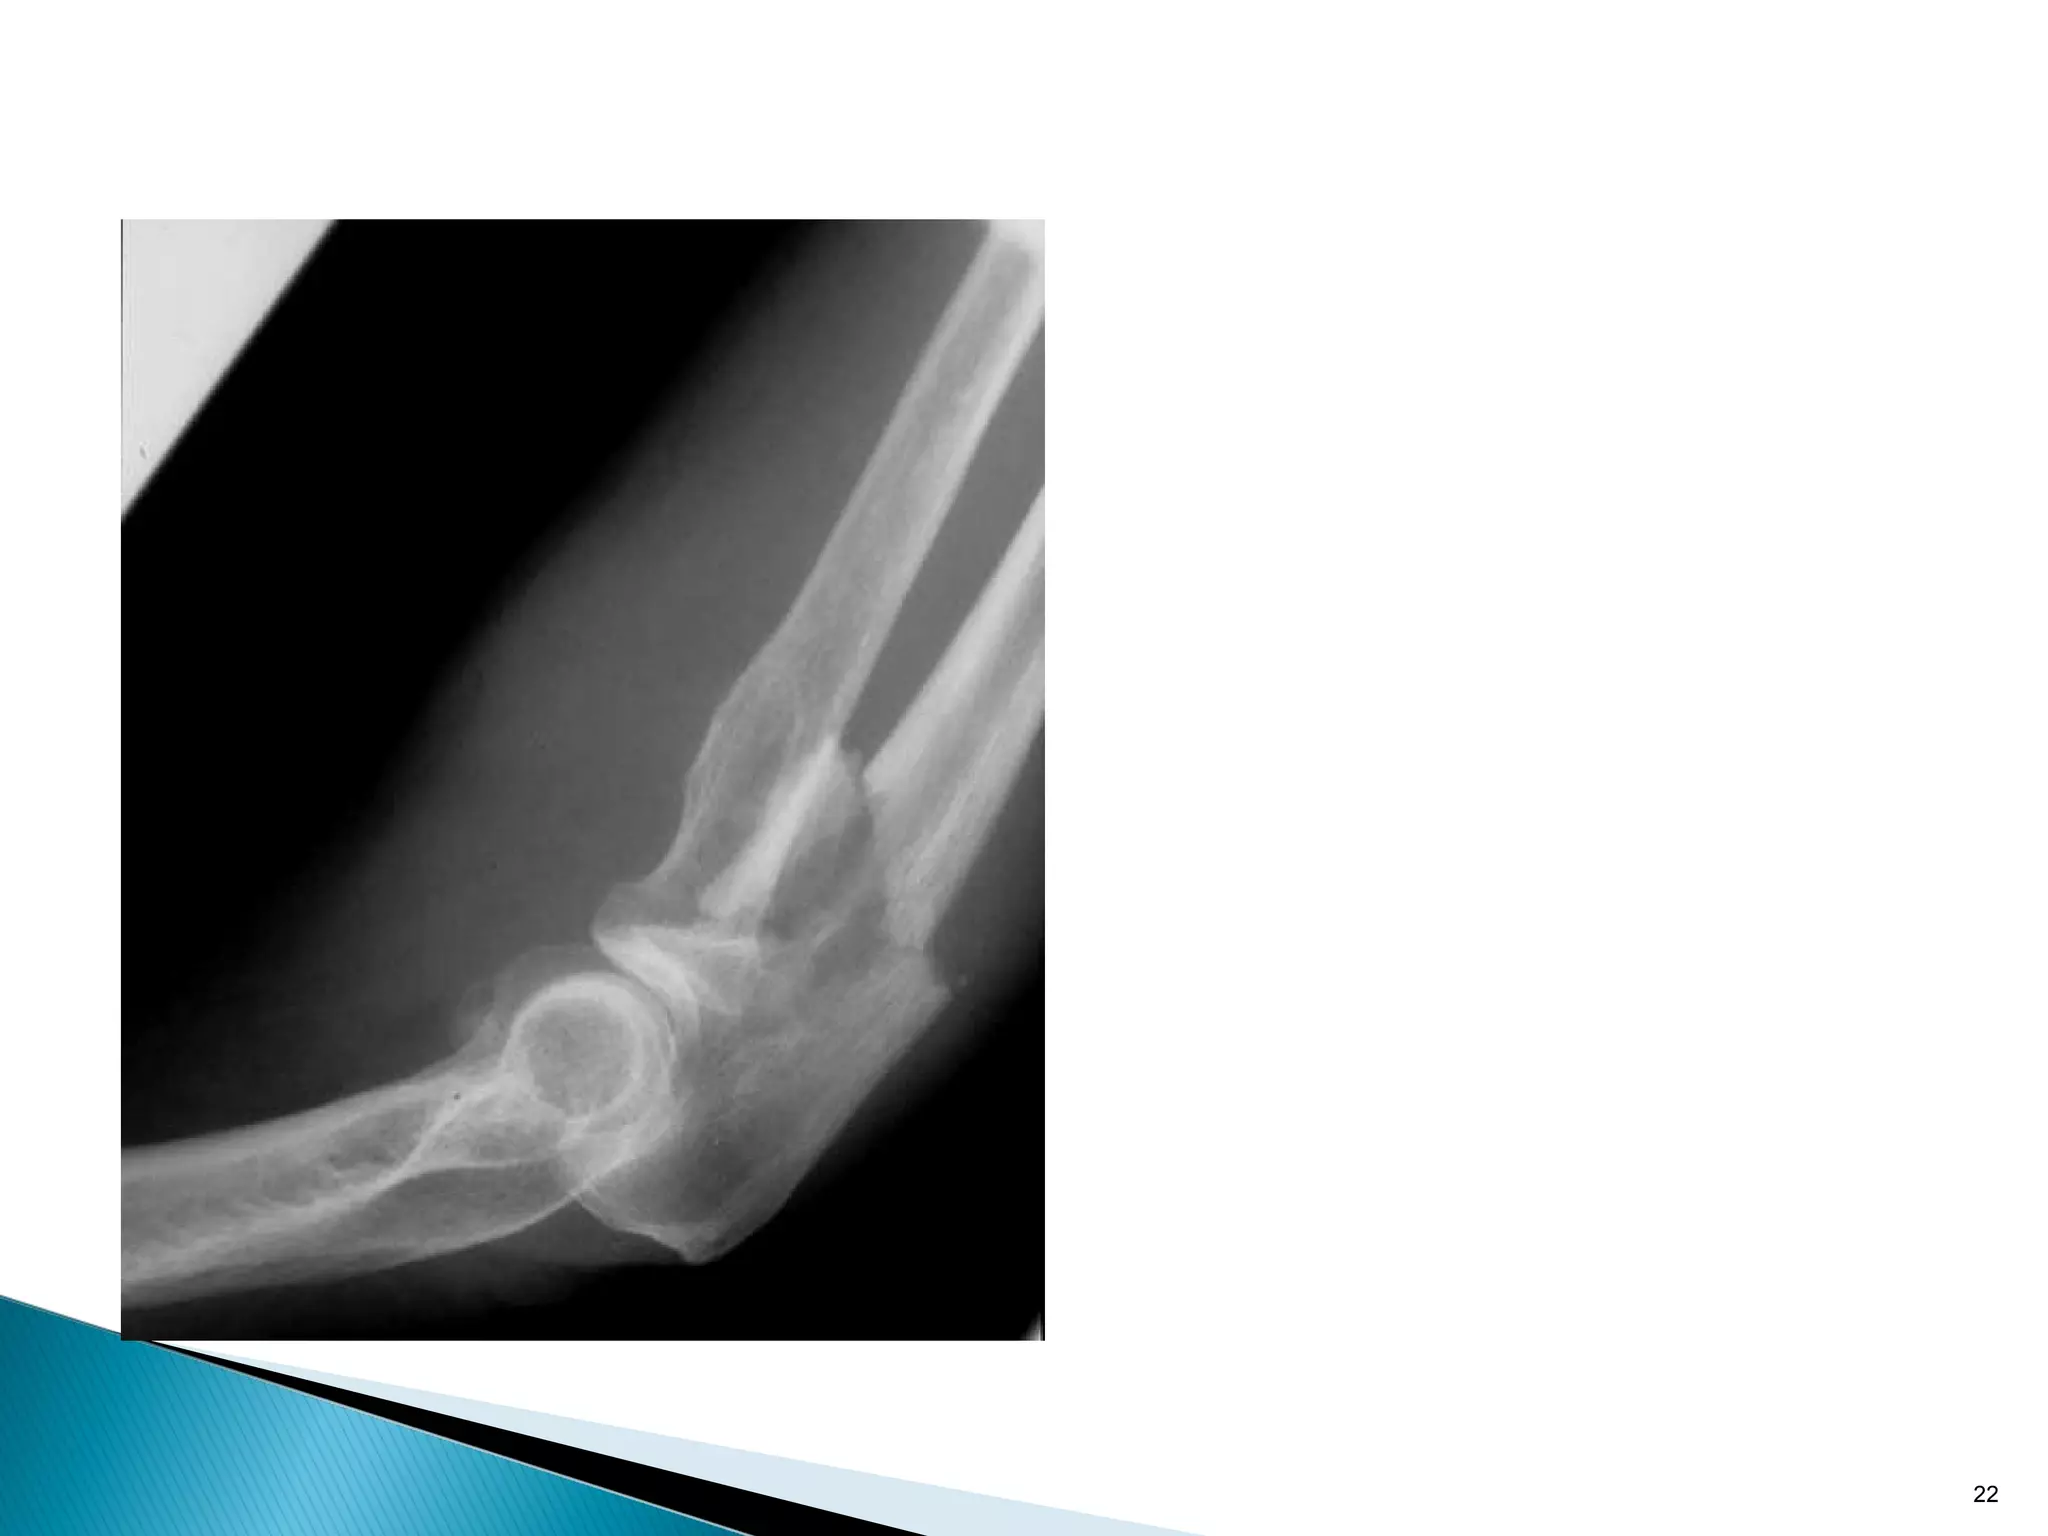

Plate on concave side distracts fracture

Absolute stability: tension band principle

22